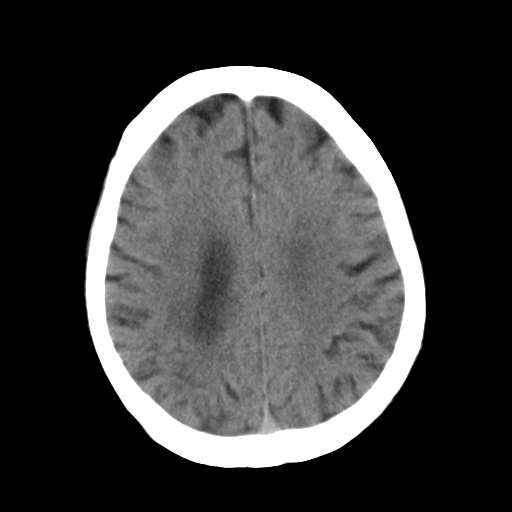

标题: CT25306:男性,75岁。右侧肢体无力一周。 [打印本页]

标题: CT25306:男性,75岁。右侧肢体无力一周。

1)右侧小脑梗塞。2)脑萎缩。